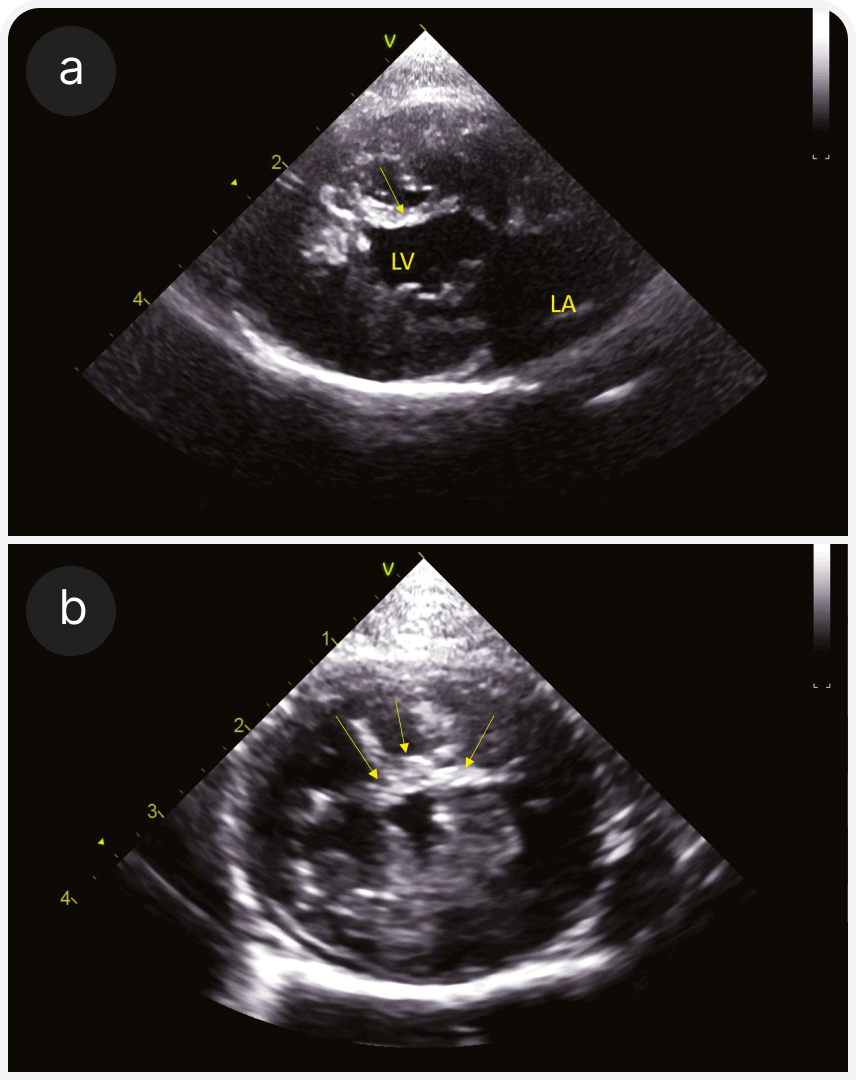

2. Рестриктивная кардиомиопатия (РКМП). РКМП без гипертрофии и расширения полостей или сопровождающаяся дилатацией левого или обоих предсердий (Рисунок 4) с диастолической дисфункцией, рестриктивным характером наполнения сердца, характеризуется более чем в два раза более высокой скоростью трансмитрального потока Е по сравнению со скоростью волны А. Обратите внимание, что эта форма диастолической дисфункции неспецифична для РКМП, но может возникать при любой кардиомиопатии. Подразделяется на миокардиальную форму (22), без особенностей эндокарда (Рисунок 4), и эндомиокардиальную форму (23, 24), при которой эндокард может быть неравномерно утолщенным и эхогенным, с рубцовыми мостиками, которые могут вызывать внутрижелудочковую обструкцию (Рисунок 5). Предрасположенность описана для кошек сиамской или ориентальной пород.

(b) Проекция RPS по короткой оси на уровне папиллярных мышц; видны предполагаемый инфаркт миокарда и фиброзное замещение у той же кошки, что и на (3a). Видна тонкая стенка ЛЖ (стрелки) между двумя папиллярными мышцами.

(b) RPS-проекция по короткой оси на уровне папиллярных мышц у той же сиамской кошки, что и на рисунке (5a). Эхогенный мостиковый рубец пересекает полость ЛЖ (стрелки).